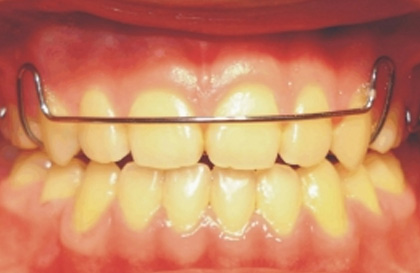

2. 赫氏上顎弓齒列固定器 ( Hawley Appliance )

牙齒細節調整定位器 ( Positioner ) 使用完成後,醫師經常給病者戴用「赫氏上顎弓齒列固定器」繼續牙齒之固定與維護 ( 下圖 ),或者矯正器拆除後,有時醫師會直接建議戴用「赫氏齒列固定器」。

赫氏上顎弓齒列固定器